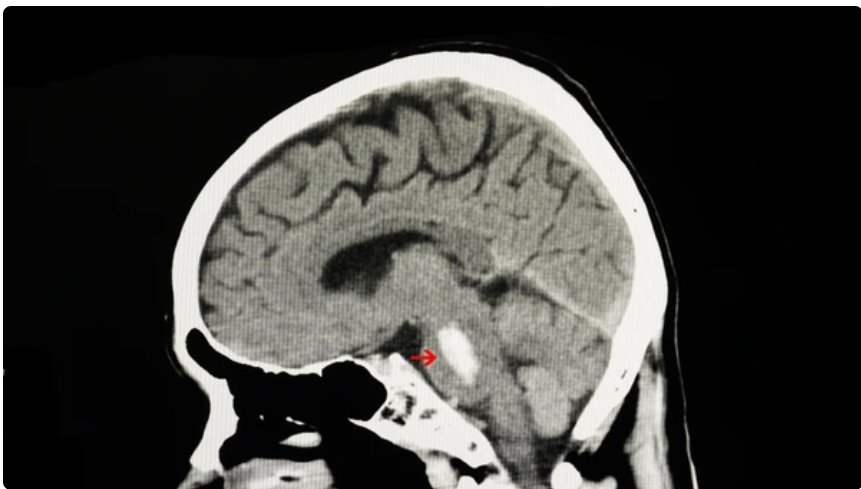

1.뇌간의 뇌교에서 발생하는 출혈로, 전체 뇌내출혈의 약 10%를 차지하지만 가장 치명적인 예후를 보이는 질환 중 하나임. 2.뇌교출혈의 가장 주된 원인은 만성 고혈압임. 3.주요 혈액 공급원은 기저동맥(Basilar artery)에서 분지되는 paramedian penetrating arteries로, 이들은 짧고 직각으로 분지되는 소동맥임.해당 혈관은 측부 순환이 거의 없어, 파열 시 출혈이 빠르게 진행됨. 4.만성적인 고혈압으로 인해 미세 혈관벽에 지방유리증(Lipohyalinosis)이나 미세동맥류(Charcot-Bouchard aneurysm)가 형성됨.혈관벽 탄성 감소 및 취약해져 급격한 혈압 상승 시 혈관이 파열됨. 이 기전이 뇌교출혈의 가장 흔한 원인임. 5.뇌교는 공간이 매우 제한적이며,..

공부 요약 2026.01.07